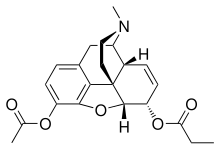

Opium alkaloids and derivatives

Phenanthrenes naturally occurring in (opium):

Esters of morphine

- Diacetylmorphine (morphine diacetate; heroin)

- Nicomorphine (morphine dinicotinate)

- Dipropanoylmorphine (morphine dipropionate)

- Diacetyldihydromorphine

- Acetylpropionylmorphine

- Desomorphine

- Methyldesorphine

- Dibenzoylmorphine